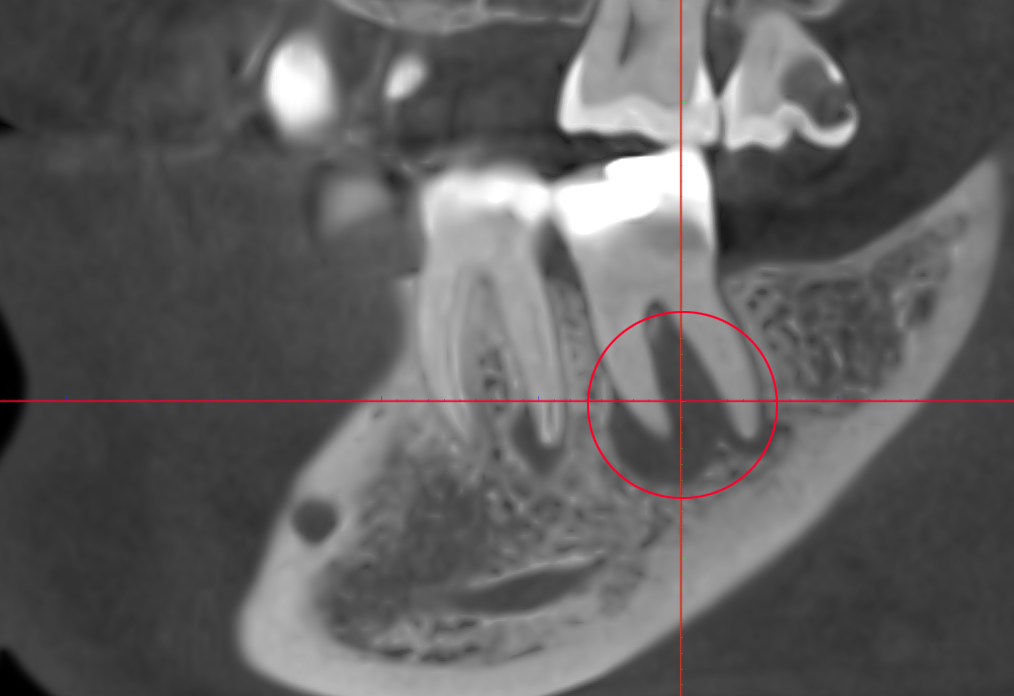

как выглядит киста зуба на кт

На компьютерной томографии (КТ), киста обычно представляет себя как округлая или овальная область с различной плотностью, чем окружающие ткани. Визуализация зависит от того, какие ткани составляют содержимое кисты и ее стенки.

Обводка кисты: Кисты часто имеют тонкую, четкую обводку, что делает их хорошо видимыми на КТ-снимках. Обводка может быть более плотной или менее плотной, в зависимости от состава тканей кисты.

Плотность содержимого: Внутреннее содержимое кисты может иметь разную плотность. Это может быть жидкость, гной, или другие материалы. На КТ-изображении жидкость обычно выглядит как темная область, в то время как более плотные материалы, такие как гной или кровь, могут иметь более светлый оттенок.

Размер и форма: КТ предоставляет детальные снимки, которые позволяют оценить размеры и форму кисты. Это важно для определения характера образования и его воздействия на окружающие ткани.

Связь с окружающими структурами: КТ также позволяет оценить, как киста взаимодействует с окружающими структурами, такими как соседние зубы, костные ткани, нервы и сосуды. Это важно для планирования лечения и определения возможных осложнений.

Общий вид кисты на КТ может сильно варьироваться в зависимости от ее типа, местоположения и стадии развития. Результаты КТ-исследования обычно анализируются специалистом, который может предоставить более детальные и точные сведения о структуре и характере образования.